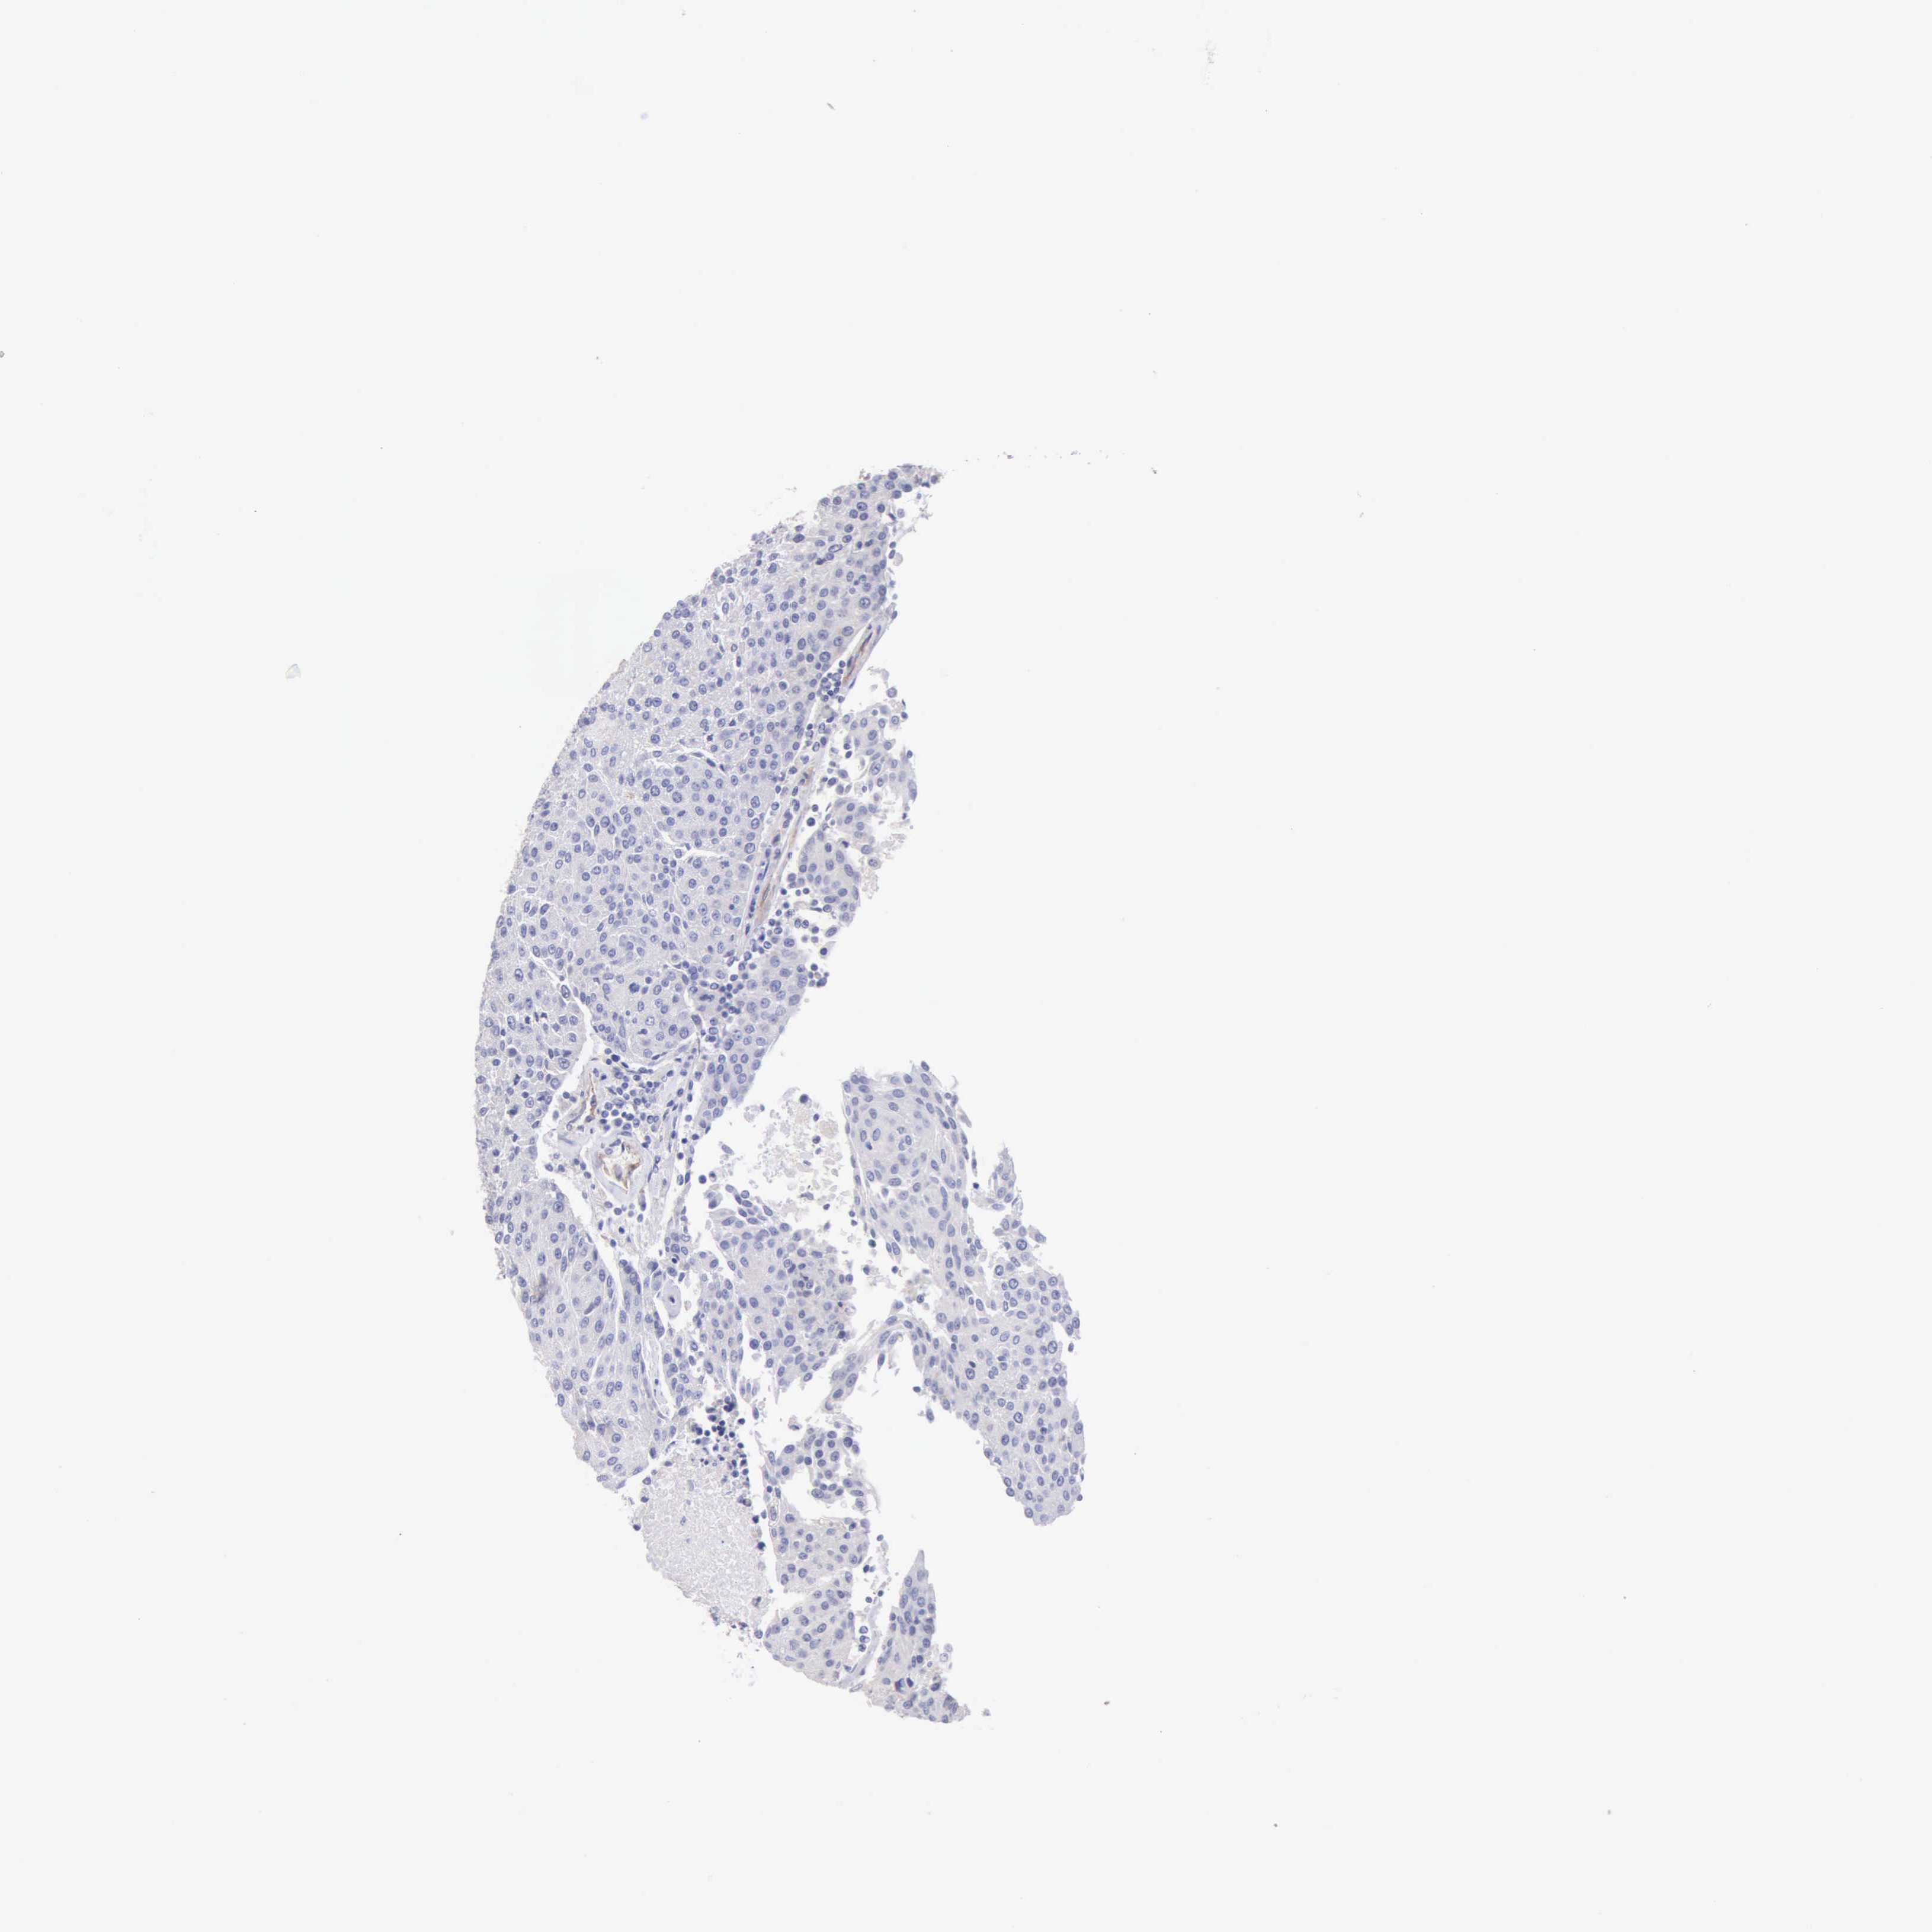

UROTHELIAL CANCER - Protein expressioni

A mouse-over function shows sample information and annotation data. Click on an image to view it in a full screen mode. Samples can be filtered based on level of antibody staining by selecting one or several of the following categories: high, medium, low and not detected. The assay and annotation is described here.

Antibody stainingi

Antibody staining in the annotated cell types in the current human tissue is reported as not detected, low, medium, or high, based on conventional immunohistochemistry profiling in selected tissues. This score is based on the combination of the staining intensity and fraction of stained cells.

Each image is clickable and will lead to virtual microscopy that enables deeper exploration of all samples and also displays staining intensity scores, fraction scores and subcellular localization as well as patient and tissue information for each sample.

Antibody HPA001462

Antibody CAB000157

Urothelial carcinoma, High grade

Urothelial carcinoma, Low grade

Adenocarcinoma, NOS